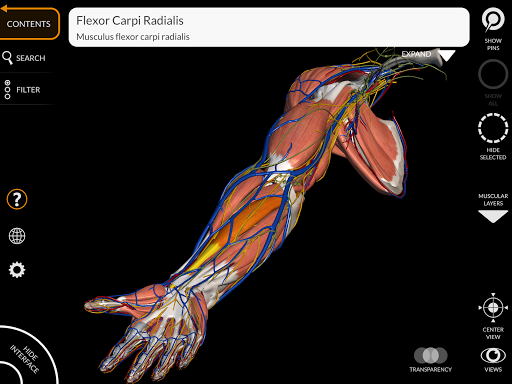

"Anatomy 3D Atlas" дозволяє легко та інтерактивно вивчати анатомію людини.

Завдяки простому та інтуїтивно зрозумілому інтерфейсу можна спостерігати кожну анатомічну структуру під будь-яким кутом.

Анатомічні 3D-моделі особливо деталізовані та мають текстури з роздільною здатністю до 4k.

• Обертайте та збільшуйте кожну модель Тривимірний простір

• Можливість приховування або ізоляції однієї чи кількох вибраних моделей

• Візуалізація м’язів через рівні шарів від поверхневих донизу до найглибших

• Вибравши модель або шпильку, з’явиться відповідний анатомічний термін